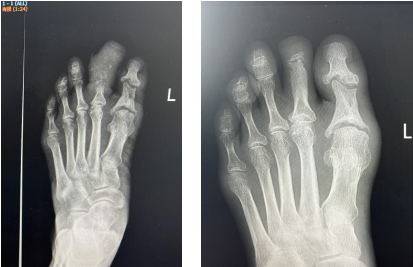

治療前后對(duì)比

3個(gè)多月后,趙阿姨回到醫(yī)院來拆掉外架,經(jīng)傷趾DR治療前后對(duì)比顯示,其左足第二趾血供明顯改善,創(chuàng)面完全愈合,傷趾還長出了新指甲,與之前腫脹、糜爛的足趾判若兩“趾”。

治療前后DR對(duì)比